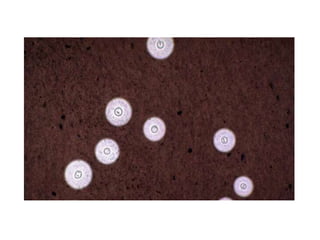

Case 4 • 32year old male • K/C/O- Retroviral disease • C/O- fever, headache x 3 days • A/w- Confusion, forgetfullness • O/E – Moderate grade fever, cranial nerves normal • Minimal nuchal rigidity, hyperreflexic • CSF- high TLC , lymphocyte predominant • India Ink - Positive

• #34 Cryptococci in perivascular space

• #35 Mucicarmine

• #36 Alcian Blue

• #37 PAS

• #38 Mucicrmine stain